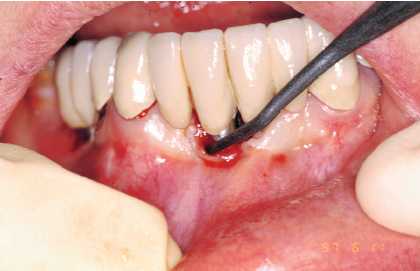

— Eliminación de placa bacteriana y/o cálculo

con curetas de plástico, oro, titanio o carbono composite

(Figura 3), puntas de ultrasonido de carbono composite (Figura

4). No se debe emplear ningún instrumento con punta

metálica, ya que se corre el riesgo de arañar

la superficie del implante y crear nichos en los que proliferen

las bacterias.

Figura 3. Limpieza de implante con cureta de carbono